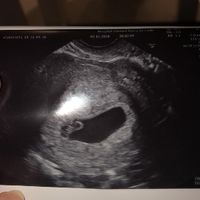

Hola chicas! Escribo este post embarazada de 5 semanas y con mucha preocupación después de un espontáneo y un diferido. Me he vuelto a quedar embarazada y en los otros dos embarazos a estas alturas...